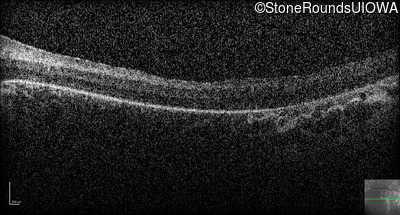

Optical Coherence Tomography - Right -

No Light Perception

Exemplar

Expanded OCT Stack

×